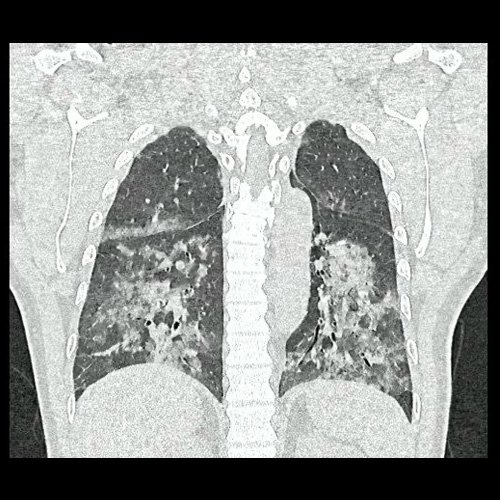

- Tomografía de tórax sin contraste endovenoso (Dia 0):Se observan múltiples áreas de consolidación parenquimatosa con broncograma aéreo y de distribución difusa por ambos pulmones, predominando en los lóbulos inferiores, asociadas a engrosamiento de los septos y rodeadas de tenue vidrio esmerilado. Se identifican estructuras ganglionares lateroaórticas, pretraqueales y subcarinales, ninguna de ellas sin alcanzar rango megálico.

Tomografia de torax sin contraste endovenosos (Ventana pulmonar- Corte coronal)

Tomografia de torax sin contraste endovenosos (Ventana pulmonar- Corte coronal)

Tomografia de torax sin contraste endovenosos (Ventana pulmonar- Corte coronal)

Tomografia de torax sin contraste endovenosos (Ventana pulmonar- Corte coronal)